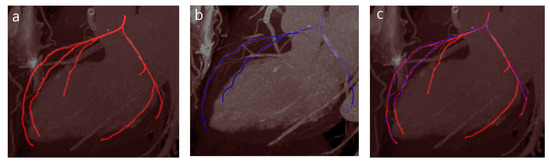

3.3. Evaluation on a CCTA Database

4. Evaluation and Results